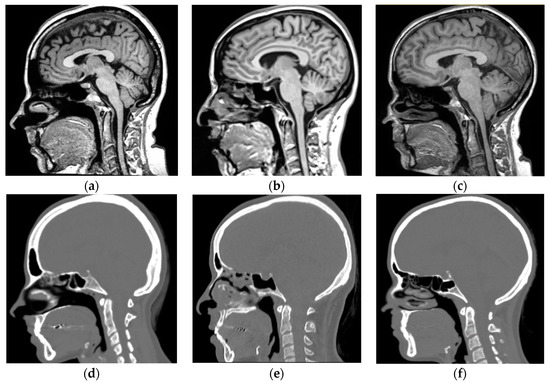

2.2. Magnetic Resonance-Computerized Tomography (MR-CT) Datasets

2.2.1. Training Dataset

2.2.2. Validation Dataset

2.2.3. Datasets Preprocessing